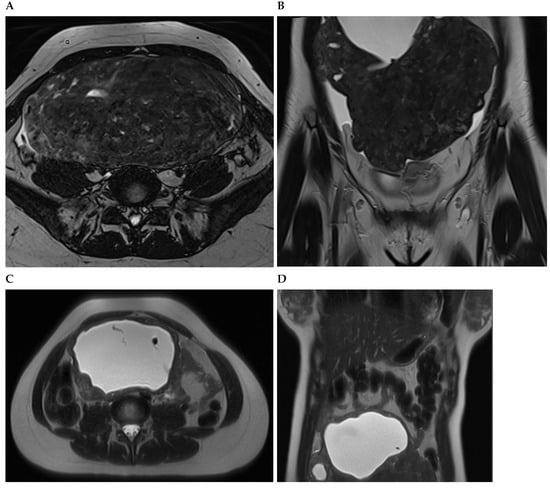

Figure 3. A woman with non-oral contraceptive user, presented to the outpatient clinic requesting a second opinion concerning a 240 mm sized uterine leiomyioma found by ultrasound at a different healthcare center. A computed tomography showed a uterine multinodular lesion with signs of degeneration. The patient received magnetic resonance imaging examination (Figure 3) and surgery with total myomectomy and specimen histopathological analyses (Figure 4). Herein, Figure 3 shows a subserosal-pedunculated leiomyoma with hyaline and cystic degeneration in a 29-year-old woman. (A) Axial and (B) coronal T2-weighted (T2) Dixon magnetic resonance imaging (MRI) showed a normal-sized uterus with axial organ rotation by 180° in an anticlockwise direction. From the right cornual region of the uterus, there was a low signal intensity (T2) subserosal-pedunculated mass (FIGO 7). This well-circumscribed, giant abdominopelvic mass measured approximately 173 × 84 × 174 mm and presented signs of cystic degeneration on its most cranial portion by demonstrating an internal, round, well-defined area with homogeneous fluid-like high signal intensity (T2), best represented on (C) axial and (D) coronal T2 half-Fourier acquisition single-shot turbo spin-echo MRI. It also demonstrated (E) low-signal intensity on non-contrast axial T1-weighted (T1) Dixon MRI, (F) without enhancement on arterial axial T1 Dixon MRI, further suggesting cystic degeneration (up to 80% of histological distribution of degeneration area) of this giant leiomyoma.